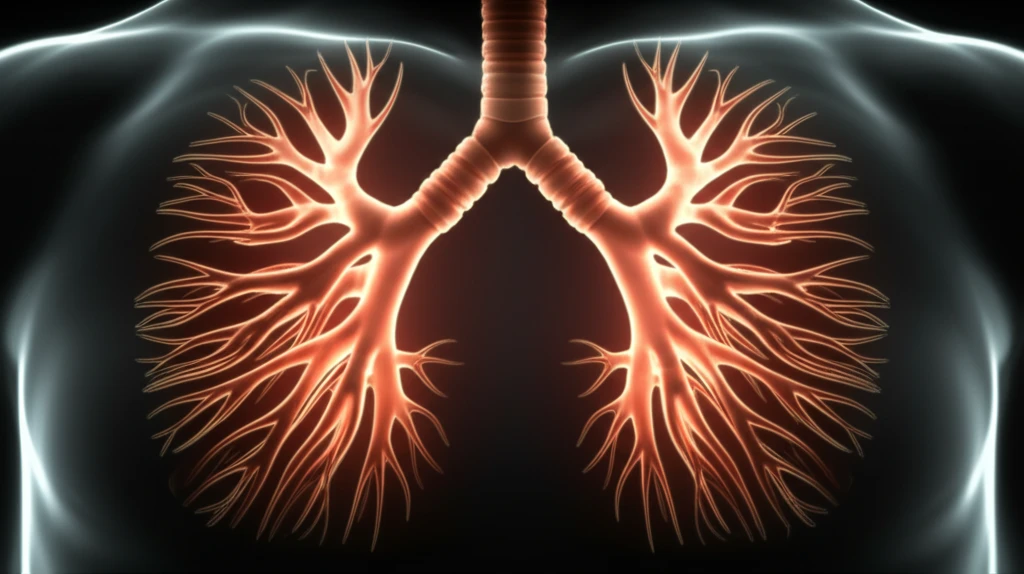

The central airway, encompassing the trachea, main stem bronchi, and lobar bronchi, is vital for breathing. When disorders strike this area, causing symptoms like cough, dyspnea, and stridor, surgery becomes a key treatment option. These surgeries, crucial for addressing conditions from stenosis to traumatic injuries and tumors, demand careful planning and execution.

Tracheal stenosis, a common reason for trachea and bronchus surgery, arises from various factors, with post-intubation and post-tracheostomy being the most frequent causes. The condition, which narrows the trachea, can also stem from congenital diseases, inflammatory conditions, infections, or tumors. Recognizing the signs and understanding the underlying causes are the first steps toward effective management.